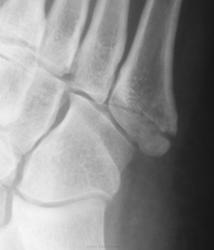

Травма.  Пациент направлен на рентгенографию стопы.

Может и в одиночестве, но ногу подвернул здорово. А перелом-то классический.

А мне не понравилась головка 2 плюсневой кости - уплощена, без видимых признаков перелома. Похоже на последствие остеохондропатии Келера?